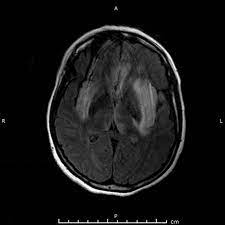

Two subtypes are recognized which differ in demographics, virus, and pattern of involvement. Become a gold supporter and see no ads. Bilateral temporal lobe t2 hyperintensity refers to hyperintense signal involving the temporal lobes on t2 weighted and flair imaging. Hypertrophic pachymeningitis is a condition where there is localized inflammatory thickening of the dura. Limbic encephalitis, mca ischaemia, tumours, effects of seizures) hyperintense t2 signal in the medial temporal lobes, inferior frontal lobes and insula basal ganglia are usually spared Reference osborn a, et al. Given the history of fever and seizures coupled with the mri findings of bilateral mesial temporal lobe changes, herpes encephalitis requires clinical consideration. The changes spare the basal ganglia, a feature which is helpful in distinguishing an mca infarct with hemorrhagic transformation from herpes simplex encephalitis, the diagnosis in this case. Mri demonstrates extensive edema in the right temporal lobe with areas of intrinsic high t1 signal, in keeping with hemorrhage. It is estimated to occur in ~2% of pati. The differential diagnoses include limbic encephalitis (paraneoplastic), gliomatosis cerebri, and status epilepticus. It is reasonable to obtain an mri when patients are asymptomatic to ensure that no other abnormality is present which may be causing a recurrent chemical meningitis (e.g. Axial t2 prominent swelling, increase t2 signal involving the left temporal lobe and insular cortex.

Mri demonstrates extensive edema in the right temporal lobe with areas of intrinsic high t1 signal, in keeping with hemorrhage. Become a gold supporter and see no ads. For a general discussion, and for links to other system specific manifestations, please refer to the article on coccidioidomycosis. This patient went on to have hsv encephalitis proven on csf pcr. This patient went on to have hsv encephalitis proven on csf pcr. Spinal hydatid disease is an uncommon manifestation of hydatid disease, caused by the larval stage of echinococcus granulosus, or less commonly e. Given the history of fever and seizures coupled with the mri findings of bilateral mesial temporal lobe changes, herpes encephalitis requires clinical consideration. Multilocularis, and describes a spectrum of disease involving the spinal cord, the spine, or both. Herpes simplex encephalitis radiology case radiopaedia mri demonstrates extensive edema in the right temporal lobe with areas of intrinsic high t1 signal, in keeping with hemorrhage. Hsv encephalitis | radiology case | radiopaedia.org. Two subtypes are recognised which differ in demographics, virus, and pattern of involvement. It is estimated to occur in ~2% of pati. Reference osborn a, et al.

Axial t2 prominent swelling, increase t2 signal involving the left temporal lobe and insular cortex. It is estimated to occur in ~2% of pati. Become a gold supporter and see no ads. This patient went on to have hsv encephalitis proven on csf pcr. A brain biopsy was performed and the histology was consistent with encephalitis. The differential diagnoses include limbic encephalitis (paraneoplastic), gliomatosis cerebri, and status epilepticus. Multilocularis.the larval stage is the cause of hydatid disease in humans 1. It is usually bilateral but asymmetrical. Spinal hydatid disease is an uncommon manifestation of hydatid disease, caused by the larval stage of echinococcus granulosus, or less commonly e. Limbic encephalitis, mca ischaemia, tumours, effects of seizures) hyperintense t2 signal in the medial temporal lobes, inferior frontal lobes and insula basal ganglia are usually spared It is reasonable to obtain an mri when patients are asymptomatic to ensure that no other abnormality is present which may be causing a recurrent chemical meningitis (e.g. 10 public playlist includes this case Pcr was repeated on the biopsy specimen and was positive for hsv.